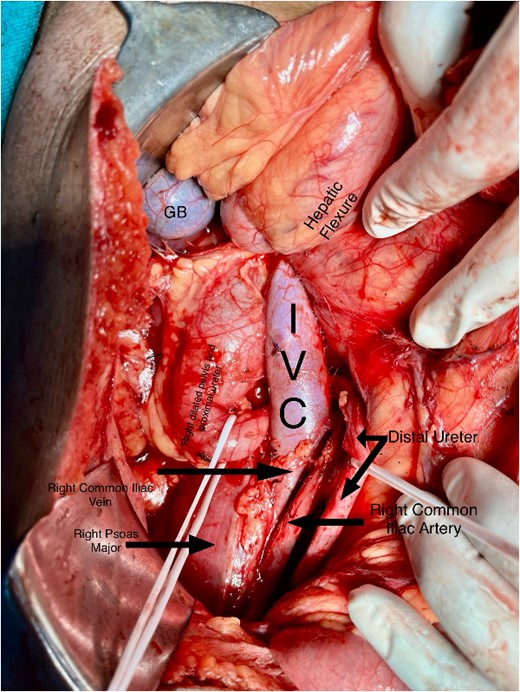

A midline incision was given, and the abdomen was opened from 4 cm below the xiphisternum to 3 cm above the pubic symphysis. The ascending colon along with the hepatic flexure was completely mobilized medially to expose the retroperitoneum. Careful dissection was done to identify the IVC and its the relations to the right ureter. The proximal dilated ureter and right pelvicalyceal system were identified, and dissection was continued laterally. The ureter was traced and noticed to course behind the IVC at the level of the L2–L3 vertebra, exiting to lie medially in the groove between the IVC and the aorta (Fig. 3). The ureter was divided proximal to the point where it coursed behind the IVC until it came out medial to IVC (Fig. 4). The retrocaval segment was brought anteriorly, resected from the normal distal ureter, and ureteropelvic anastomosis was done using 3–0 Polyglactin sutures lateral to the IVC (Fig. 5). This procedure eliminated the compression on the ureter. An abdominal drain was placed.

Intraoperative image showing pelviureteric anastomosis after resection of retrocaval part of the ureteric segment.